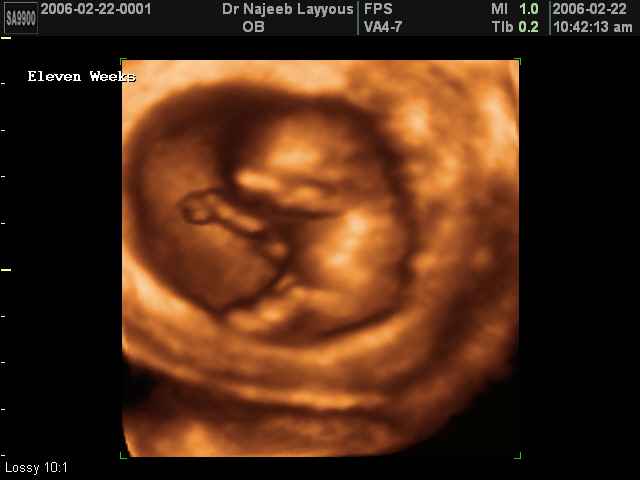

- First Trimester Ultrasound Photos

3D First Trimester Ultrasound Scan Photos ( Early Pregnancy Ultrasound Photos ) | Dr N Layyous